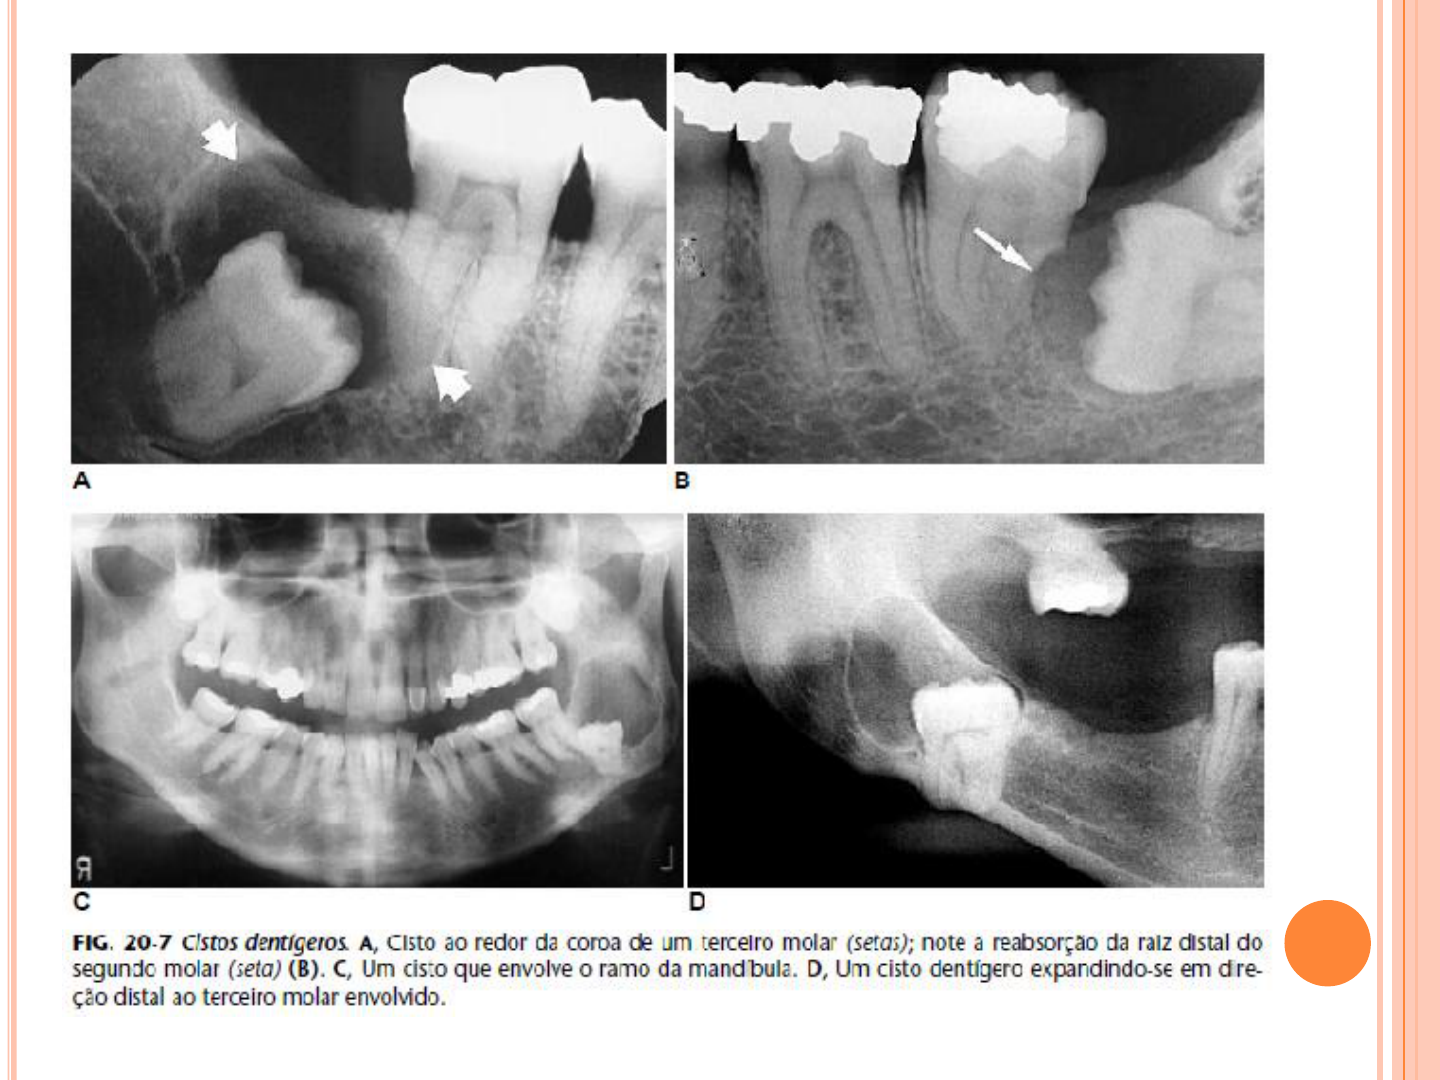

ESTUDONTO: Lesões associadas ao osso - parte 1

image size: 1200x1724

Osteomielitis Crónica Supurativa en Maxilar Superior: Informe de Caso - Studocu